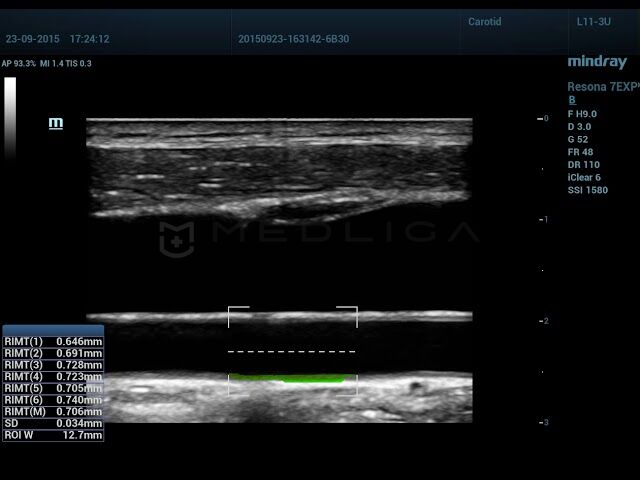

Программное обеспечение для автоматического расчета толщины комплекса интима-медиа радиочастотным методом (в реальном времени).

Автоматическое измерение комплекса интима-медиа - удобный инструмент для специалиста ультразвуковой диагностики. Mindray делает использование этой функции еще более комфортной, обеспечивая высокую точность измерений.

Определение размера КИМ - основной маркер для определения риска сердечно-сосудистых патологий. Практически все разработчики УЗИ сканеров вносят в функционал оборудования автоматические и ручные алгоритмы для измерения толщины стенки сонной артерии. Для осуществления измерений IMT применяется постобработка кинопетли, что в свою очередь имеет некоторые ограничения. Mindray разработали технология RIMT, с инновационными алгоритмами обработки полученных данных сканирования и гарантирует точное измерение комплекса интима-медиа.

Сравнение технологии RIMT и обычного режима IMT

• RIMT - новейшая технология и в разы превосходит традиционные измерения, например, точность RIMT выше в 16 раз, так как при RIMT происходит измерение ИМТ 6 сердечных циклах, а не 1 как при обычном IMT.

• RIMT (M) - средний показатель за 6 циклов

• SD - стандартное отклонение

• ROI W - ширина исследуемой области